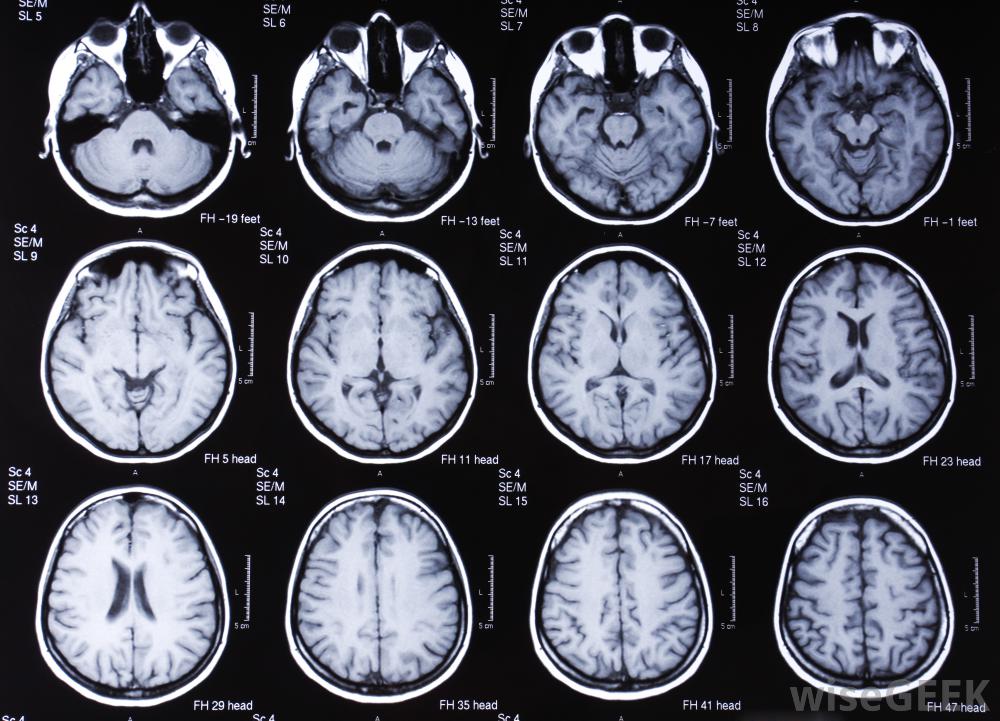

對大腦進行核磁共振掃描。

核磁共振掃描及其無線電波通過重新定位細胞核來改變人體的原子。隨著人體原子的移動,任何組織的圖像都是由計算機掃描產生的含有少量氫的組織,如骨骼,被視為一個黑暗區域,而擁有最多氫原子的組織,如軟組織,則變得更輕。

通過制作各種人體組織的詳細圖片,核磁共振掃描是發現腫瘤和檢查大腦和脊髓的最佳技術之一,MRI掃描已成為確定腦組織異常的最佳技術之一,對于發現心臟缺陷和身體內部器官的其他潛在并發癥也非常有效。